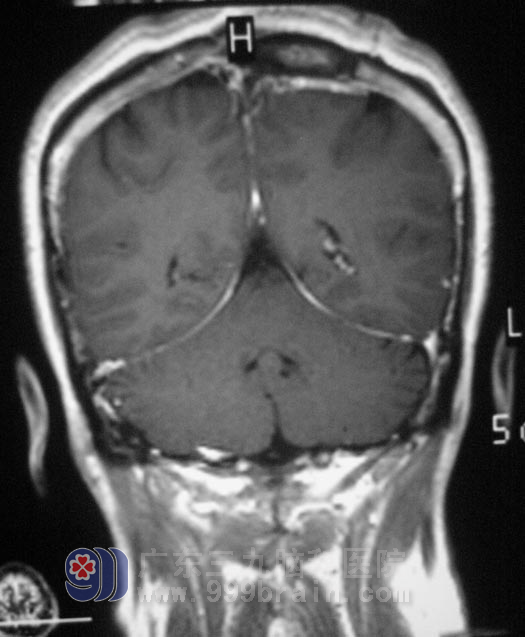

4月19日,由鲁明主任主刀,在全麻下为赵女士行左侧额顶镰窦旁占位性病变切除+颅内压探头置入术,导航定位,术中可见肿瘤侵袭硬膜,近矢状窦硬膜破坏,肿瘤深入窦内,肿瘤基底部位于矢状窦内,显微镜下全切除肿瘤。

术前担心的情况术后都没有发生,赵女士肢体活动、语言功能都保存完好,术后病理结果为:(左额顶)纤维型脑膜瘤,WHO I级。现已康复出院。

▲手术后